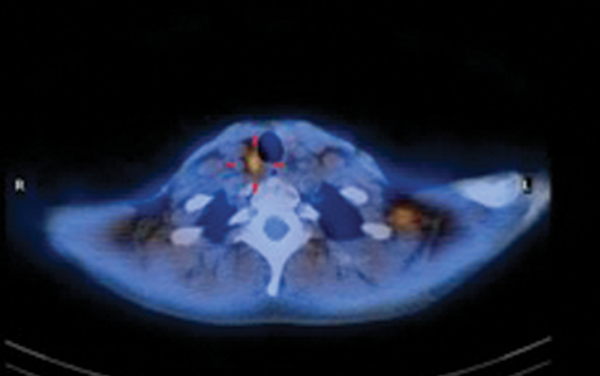

The procedure involves subcutaneous injection of radio-labelled colloid into the tissue parenchyma around the tumour. The regional drainage of the radiopharmaceutical follows that of the primary tumour and hence the SLN can be identified by dynamic and static imaging using a nuclear medicine gamma camera. Most (>95%) of the injected activity remains localised to the injection site but after a period of time a series of ‘hot spots’ appear and the SLN is identified as the first focus of tracer accumulation (Figure 2). The site of the SLN is marked on the skin to assist the surgeon in locating it at the time of surgery. SLN removal can be aided by intraoperative use of a handheld gamma probe; the nodes with the highest count reading are removed as well as any adjacent nodes with more than 10% activity. The level of radiation exposure for the surgeon, theatre staff and histopathologist involved is very low. SLN biopsy carries a lower morbidity than formal lymph node dissection and is a useful aid in staging of cutaneous cancer and directing management decisions.

Figure 2: Axial CT (top right). Fused SPECT / CT (bottom right) and lymphoscintigraphy (left)

images demonstrating localisation of a right cervical sentinel lymph node.